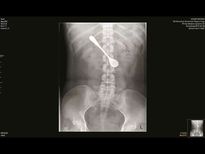

വിഴുങ്ങിയത് 5 ഇഞ്ചിന്റെ സ്പൂണ് പക്ഷേ സംഭവിച്ചത്